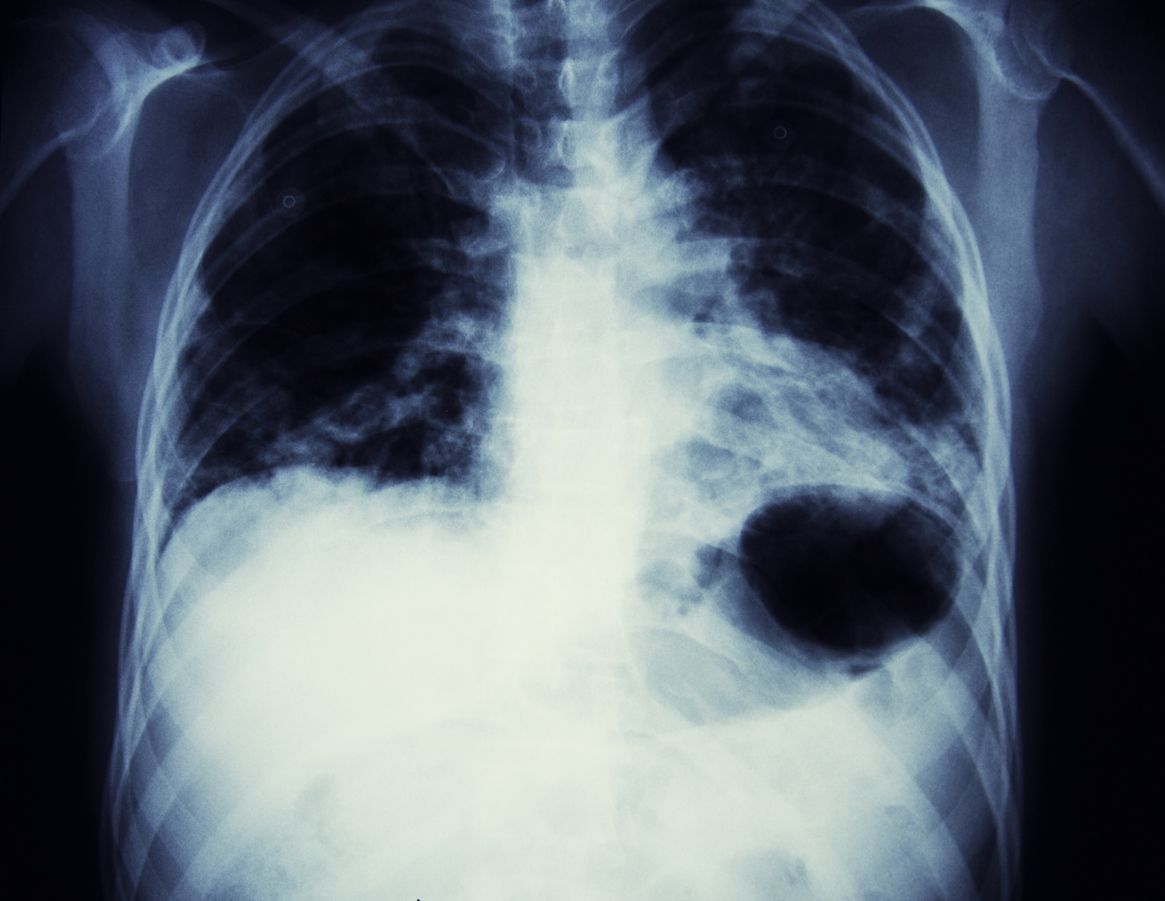

Für die Studie werteten die Forscher die Akten von mehr als 460.000 Patienten in England, Südkorea und Taiwan aus.